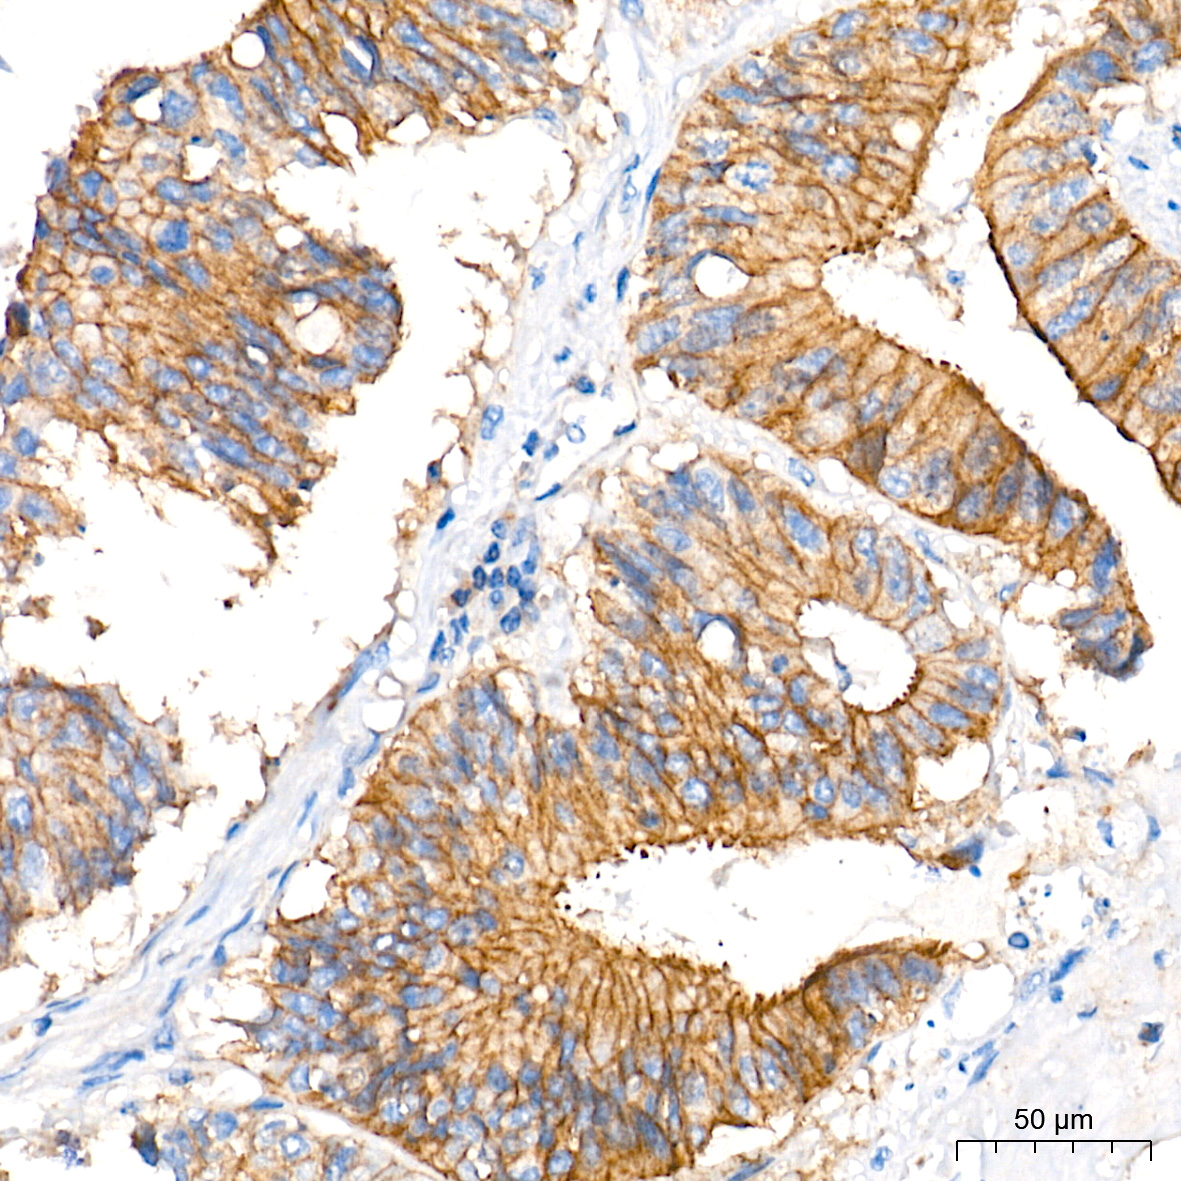

| Immunohistochemistry analysis of paraffin-embedded Human liver cancer tissue using [KD Validated] MCT1 Rabbit mAb (A27270) at a dilution of 1:600 (40x lens). High pressure antigen retrieval performed with 0.01M Tris-EDTA Buffer (pH 9.0) prior to IHC staining. |